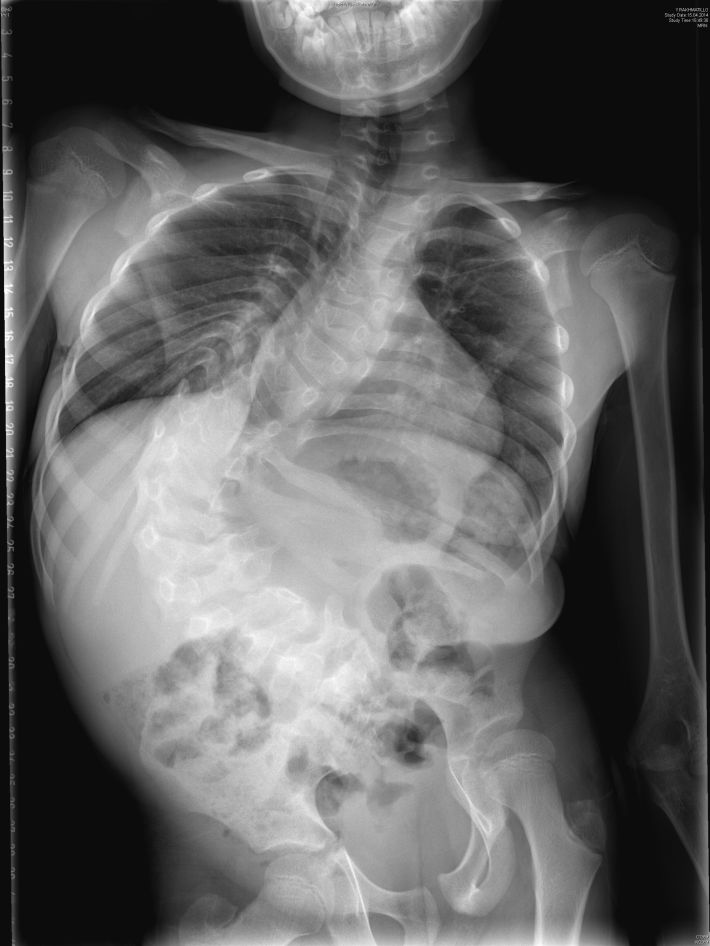

Băiețelul, în pofida vârstei fragede şi a staturii mici, a dat dovadă de multă maturitate. Toate problemele pe care le-a dus în spate l-au maturizat. Rakhmatillo, în vârstă de 11 ani, era din naştere bolnav de scolioză. Cel mai mic dintre cei doi copii. Fratele lui mai mare, în vârstă de 14 ani, era sănătos, alerga, se juca, mergea la şcoală fără probleme şi încerca să îl facă pe fratele său să uite de durerea provocată de boală. İnima familiei era îndoită de ani de zile ca şi coloana vertebrală a lui Rakhmatillo, care avea un grad de înclinare de 110 de grade. Când priveai din spate avea aspectul literei C! Ani de zile au încercat să găsească o rezolvare în Uzbekistan, nu au omis nici o uşă la care să nu bată, au fost la toţi doctorii din țară. Cu toate acestea nici unul din doctori nu a vrut să facă intervenţia chirurgicală datorită riscului ridicat de paralizie.

Micul băieţel a avut probleme nu doar la coloana vertebrală, ci şi la măduva spinării. Aderenţele şi tensiunea creată în măduva spinării au dus la slăbirea piciorului stâng şi a cauzat pierderea puterii în picior. Ruperea unor aderenţe sunt importante din două motive. Primul este acela că, în cazul în care nu se deschide va duce la pierderea totală a capacităţii de a merge aflată deja la limită şi nu îşi va mai putea controla urinările. Al doilea motiv este acela că, în cazul în care se efectuează o intervenţie de modificare a coloanei vertebrale fără să fie deschise aderenţele, aceasta ar putea cauza paralizia. Din acest motiv Prof. Dr. Memet Özek a realizat intervenţia chirurgicală asupra măduvei spinării. După o lună, Prof. Dr. Ahmet Alanay a reuşit să remedieze printr-o operaţie de succes, care a durat 7 ore, cu ajutorul unei metode ce a dus la relaxarea coloanei prin tăierea unor bucăţi de os de la nivelul coloanei vertebrale, înclinarea coloanei care nu putea fi remediată prin metode normale şi extrem de avansate. Prof. Dr. Alanay afirmând faptul că “înclinarea coloanei la 110 grade a fost redusă la 25 de grade şi a fost redusa diferenţa piciorului, care era mai scurt datorită înclinării. A mai rămas doar problema cu piciorul scurt puţin din naştere, lucru ce va putea fi remediat dacă sub talpă se adaugă o “întăritură” subliniază un punct foarte important: ”copilul, care avea o înclinare a corpului de 110 grade şi o aderenţă la măduva spinării ar fi avut probleme respiratorii serioase la vârsta de 20 de ani, ar fi avut probleme în ceea ce priveşte controlul urinărilor şi probabil şi-ar fi pierdut în totalitate funcţiile locomotorii. Dar, starea de sănătate a lui Rakhmatillo este îmbunătăţită. Acesta a revenit la o viaţă normală. Îmi trimite poze în mod constant si nu poate fi descris sentimentul de mulţumire pe care fericirea îl dă.”